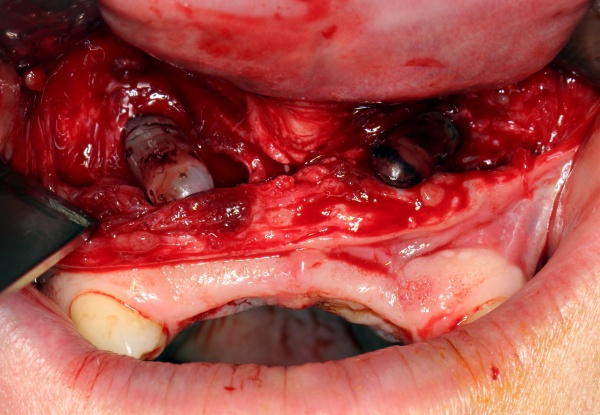

Nach Genehmigung des Antrages erfolgte im März 2012 die Extraktion aller Zähne (Abb. 1).

Im August 2012 erfolgten die 3D-gestützte Implantation (6 Implantate, Firma Nobel Biocare, System Active) im Oberkiefer mit Bone Split sowie eine An- und Auflagerungsosteoplastik vom linken Beckenkamm im Unterkiefer nach Entfernung der Miniimplantate (Abb. 3). Nach komplikationsloser Einheilung wurde im Dezember 2012 die Materialentfernung und Implantation im Unterkiefer (6 Implantate, Firma Nobel Biocare, System Active) durchgeführt (Abb. 4). Die Osseointegration verlief ungestört. Aufgrund der ungenügenden Weichgewebssituation im Unterkiefer erfolgte an jedem Implantat bei Freilegung eine Vestibulumplastik mit Einlagerung einer bioresorbierbaren Membran (Firma Botiss, Mucoderm, Abb. 5 und 6). Die endgültige prothetische Versorgung erfolgte durch den truppenzahnärztlichen Kollegen in der Stammeinheit des Patienten (Zahnarztgruppe Nordholz / SanZ Celle) mit einer gaumenfreien implantatgetragenen Teleskopprothese im Ober- und Unterkiefer, die eine festsitzend-herausnehmbare vollständige stomatognathe Rehabilitation des Patienten ermöglichte (Abb. 7 und 8). Er wurde zum halbjährlichen Recall angehalten.